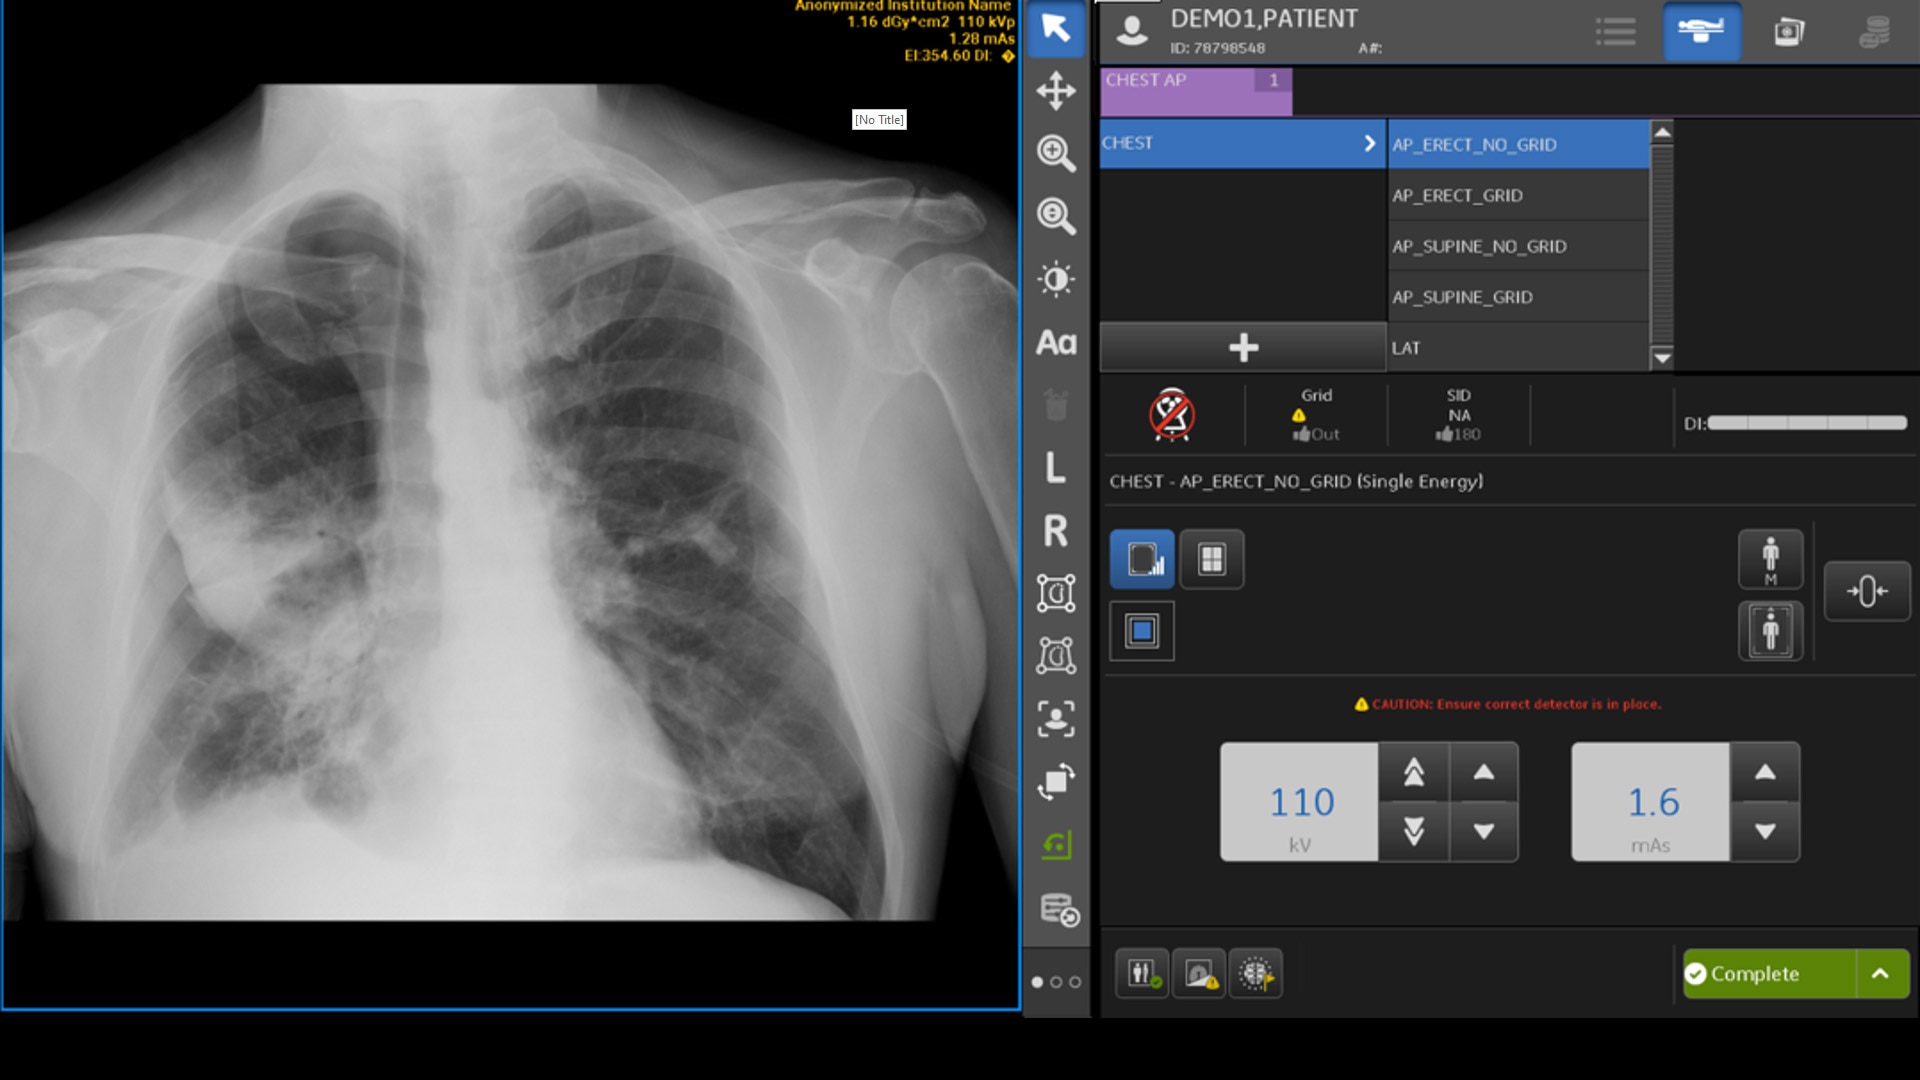

INTELLIGENT PROTOCOL CHECK

Intelligent Protocol Check conducts an automated quality check to detect errors on the acquisition system, such as a mismatch between the protocol used and the anatomy that was acquired.2 The system assists technologists by notifying them of the mismatch, allowing corrective action to be taken.